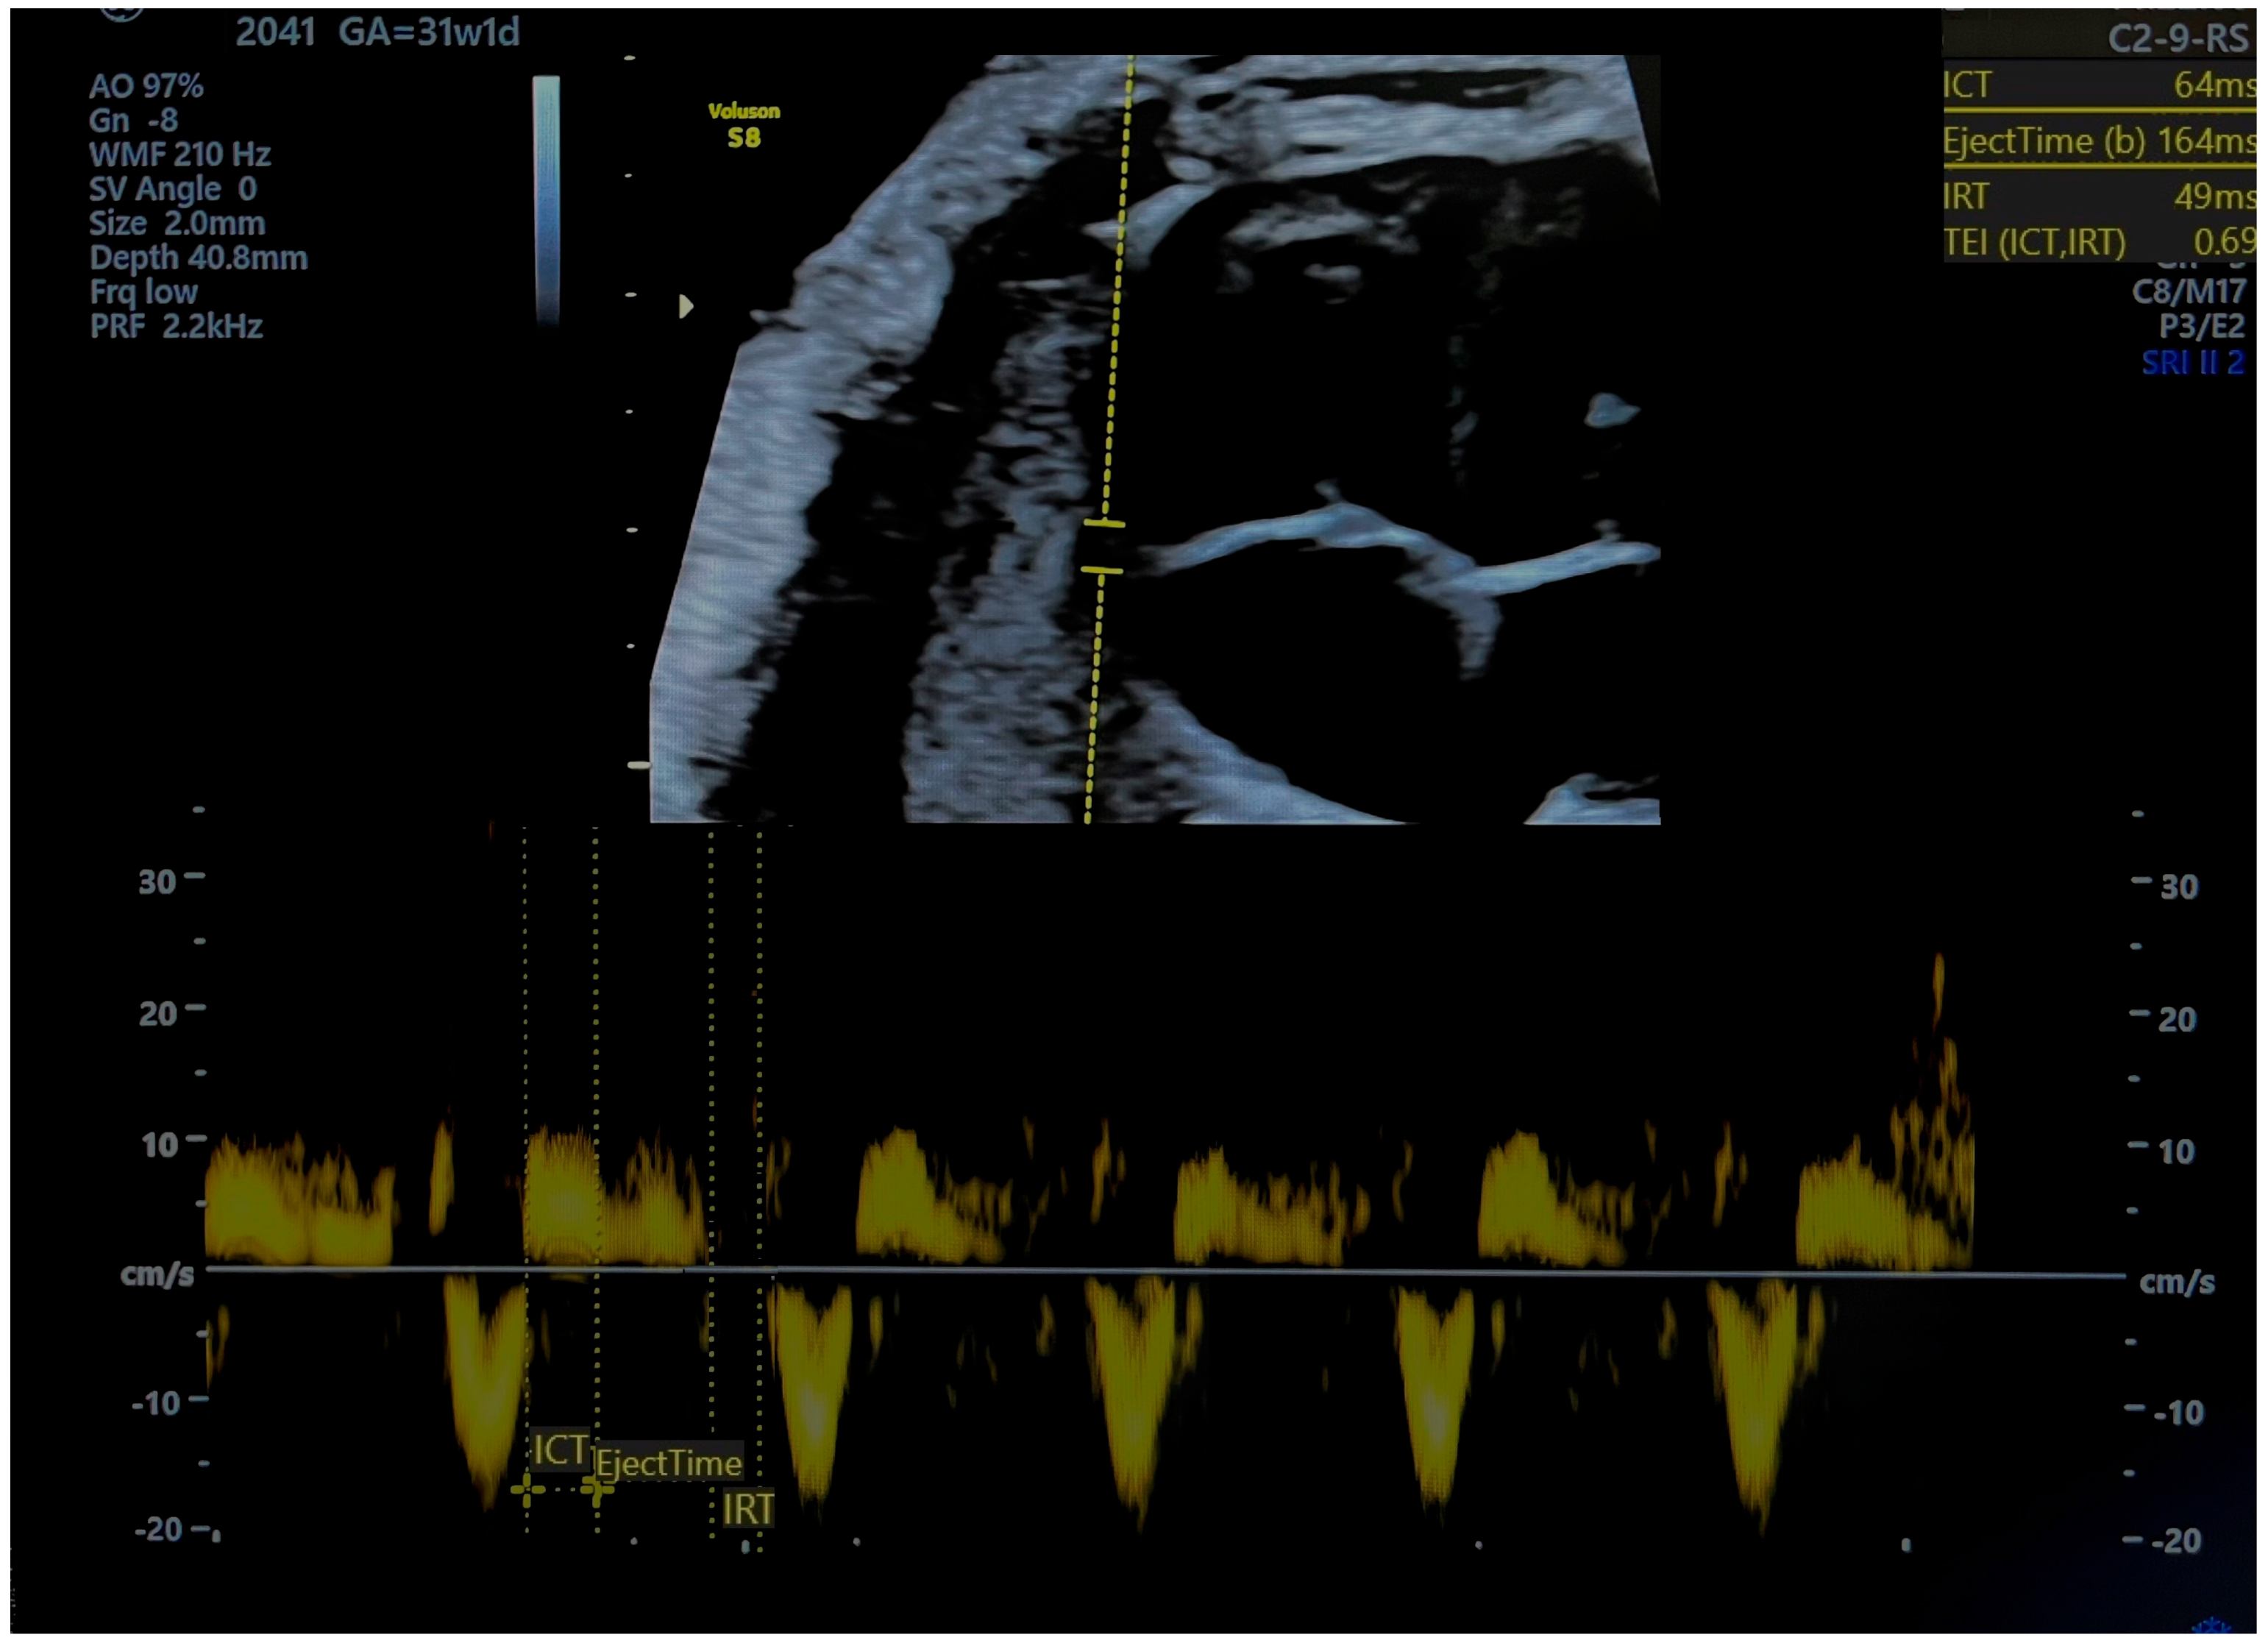

| RMPI TDI Values: Average 0.36 (0.28–0.44). Normal RMPI cut-off: 0.47 and below. | RMPI TDI Values:

| Timing: MPI alters before AoI and DV by 26, 12, and 5 days before delivery, respectively, which means that diastolic dysfunction occur prior to hypoxia. | Timing: MPI becomes altered before AoI and DV flow, which means that diastolic dysfunction occurs prior to hypoxia. |

Cardiac Impairment:

| Cardiac Impairment:

| Predictive Value: A proportion of fetuses classified as SGA have increased MPI values; therefore, these fetuses may suffer true growth restriction, and the MPI becomes altered before changes in the blood flow reach cut-off values for FGR. |